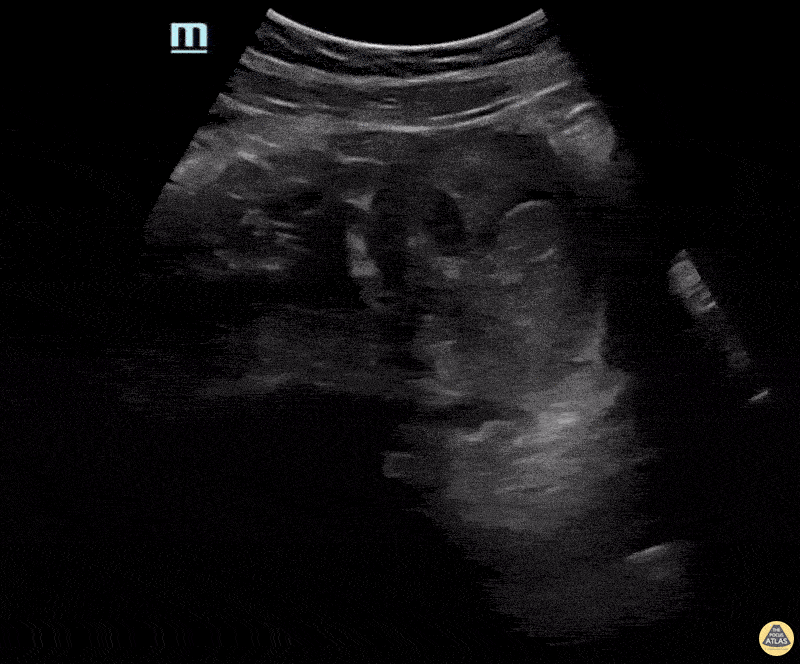

Patient was having significant nausea and vomiting and went to her local ER. While there her beta HCG was much higher than expected at her gestational age. Ultrasound shows a large amount of heterogeneous material with possible gestational sac. Confirmed after D&C. Michael Bernard, DO